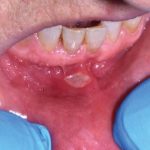

Fig. 7B Caso clinico di paziente che ha sviluppato lesione aftoso-simile a livello della mucosa alveolare in seguito alla assunzione di farmaci antipertenasivi.

Home L’odontoiatria e le reazioni avverse a farmaci delle mucose orali Fig. 7B Caso clinico di paziente che ha sviluppato lesione aftoso-simile a livello della mucosa alveolare in seguito alla assunzione di farmaci antipertenasivi.